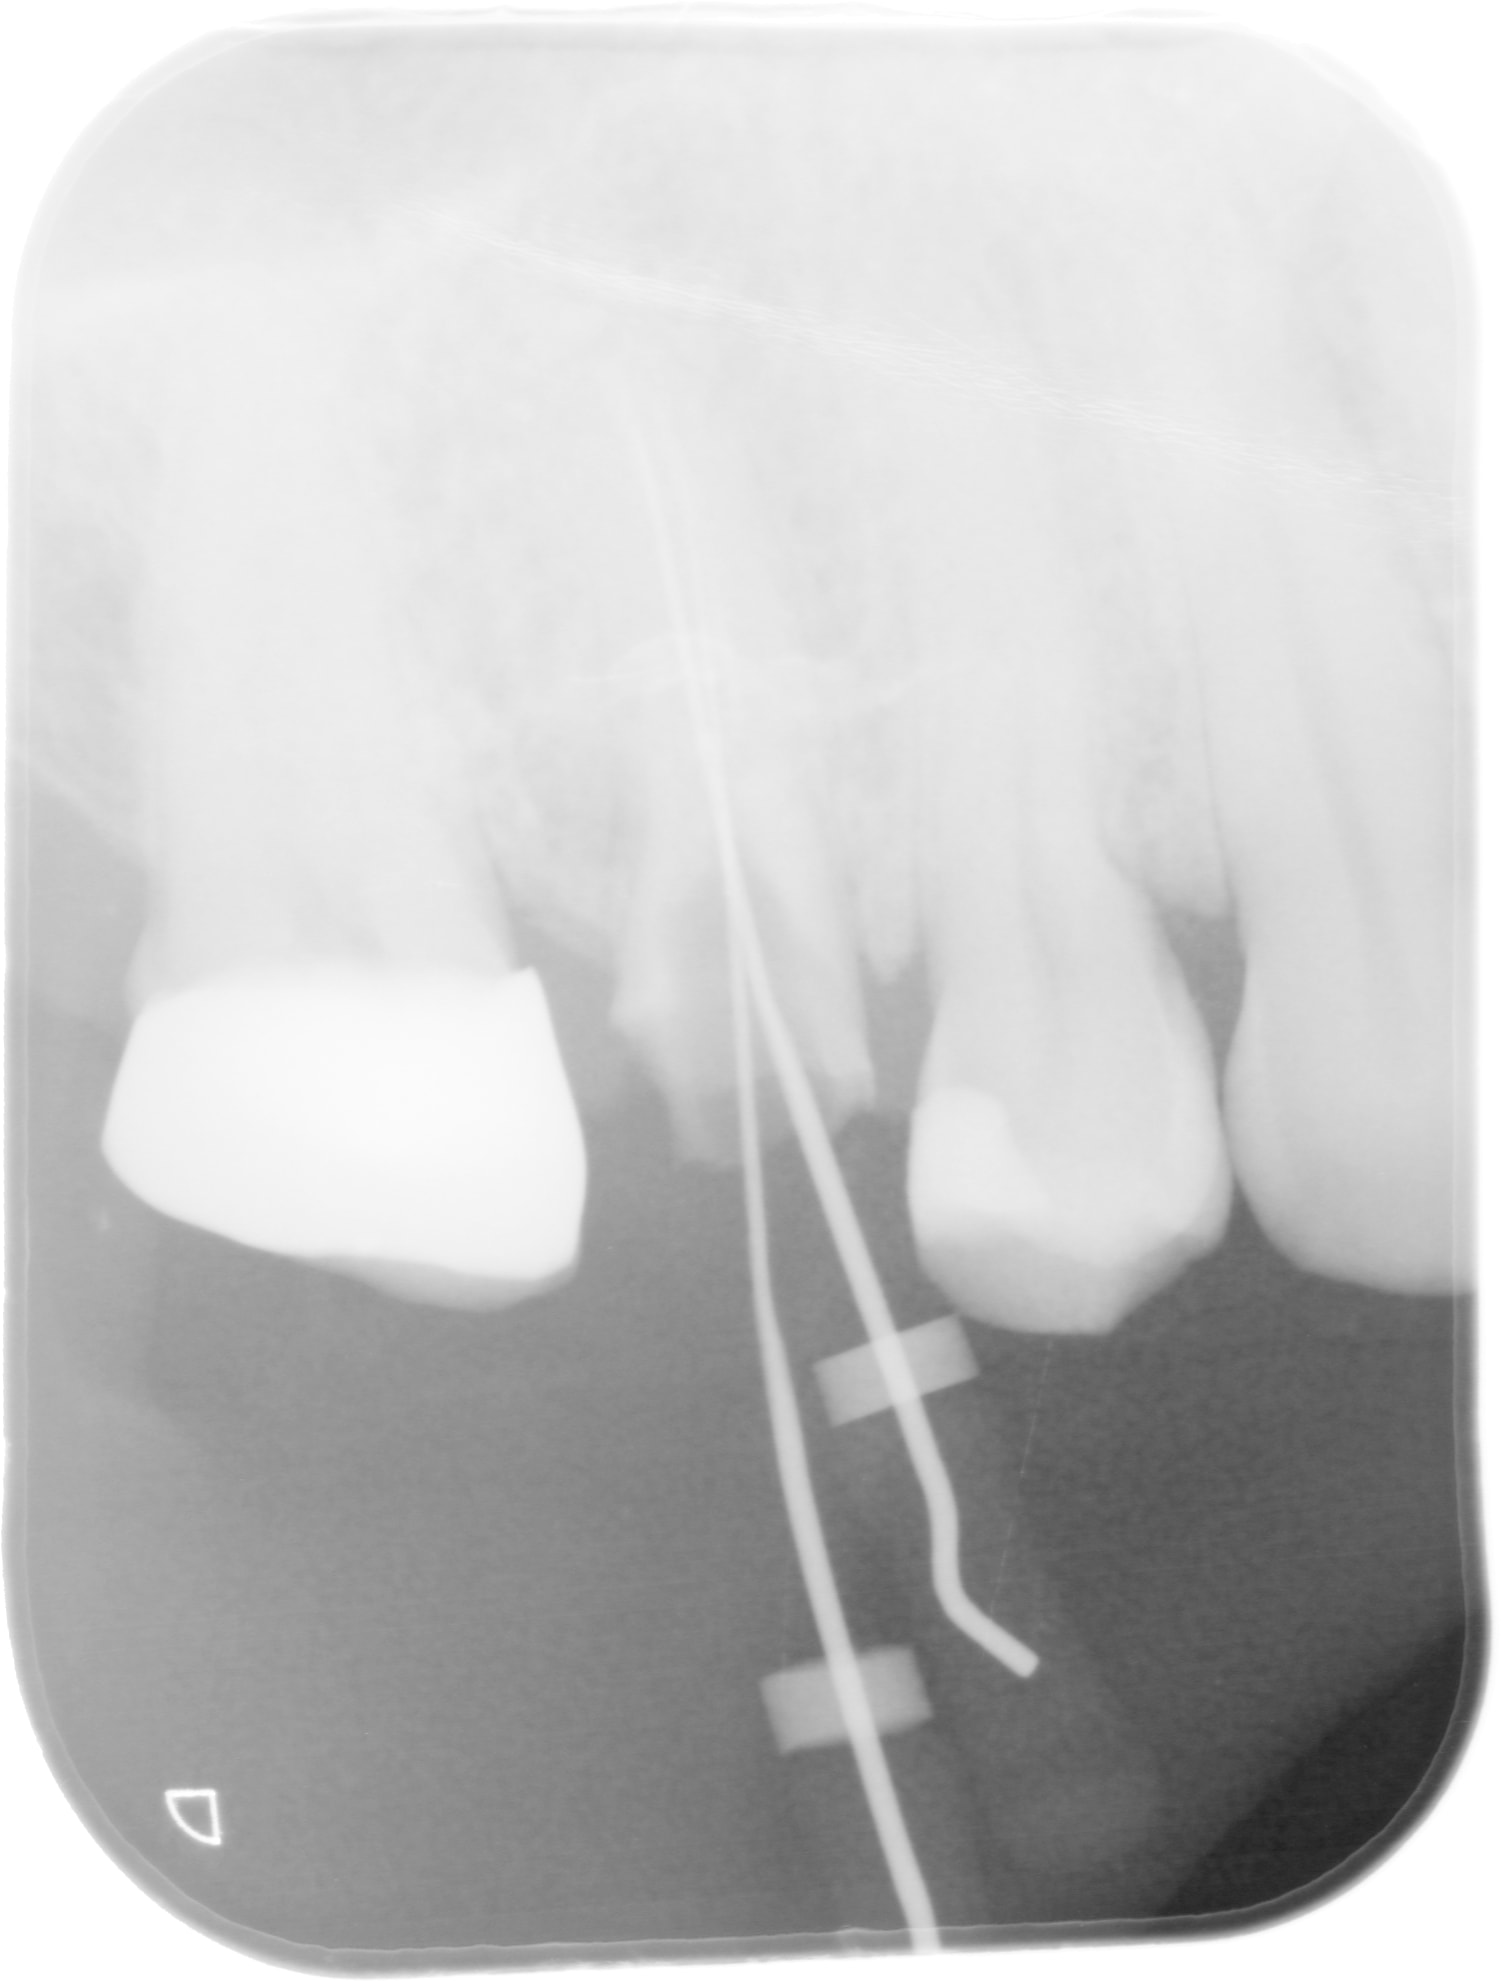

cone un peu court en mésial )))

et surtout pourquoi depulper cette dent si ce n'est pour en faire un pilier de bridge ?

fêlure sous amalgame jusqu'à corne pulpaire...

j'ai un peu peur que la fêlure ne soit plus étendue que ca : l'épaississement mésial n'est pas de bonne augure

Allez soyons positif, elle est versée, cela a fêlé... TO? épaississement.

Je te l'ai dit tant que ce n'est pas séparé ou douloureux à la pression je tente. Et puis à force d'essayer je vais bien trouver un truc, LE truc pour ce genre de cas. Hier c''était une 14, fêlure sous compo... comme quoi... Jolie fêlure en mésiale, en distal je ne sais pas il n'y a plus de parois, je vais mettre deux tenons bien hauts + compo, le tout en un bloc (collage compo tenon)+ CR qui vivra verra, le patient est informé, il va réfléchir.

Oui, rien de notable, pas de zone d'enfoncement "étroite"